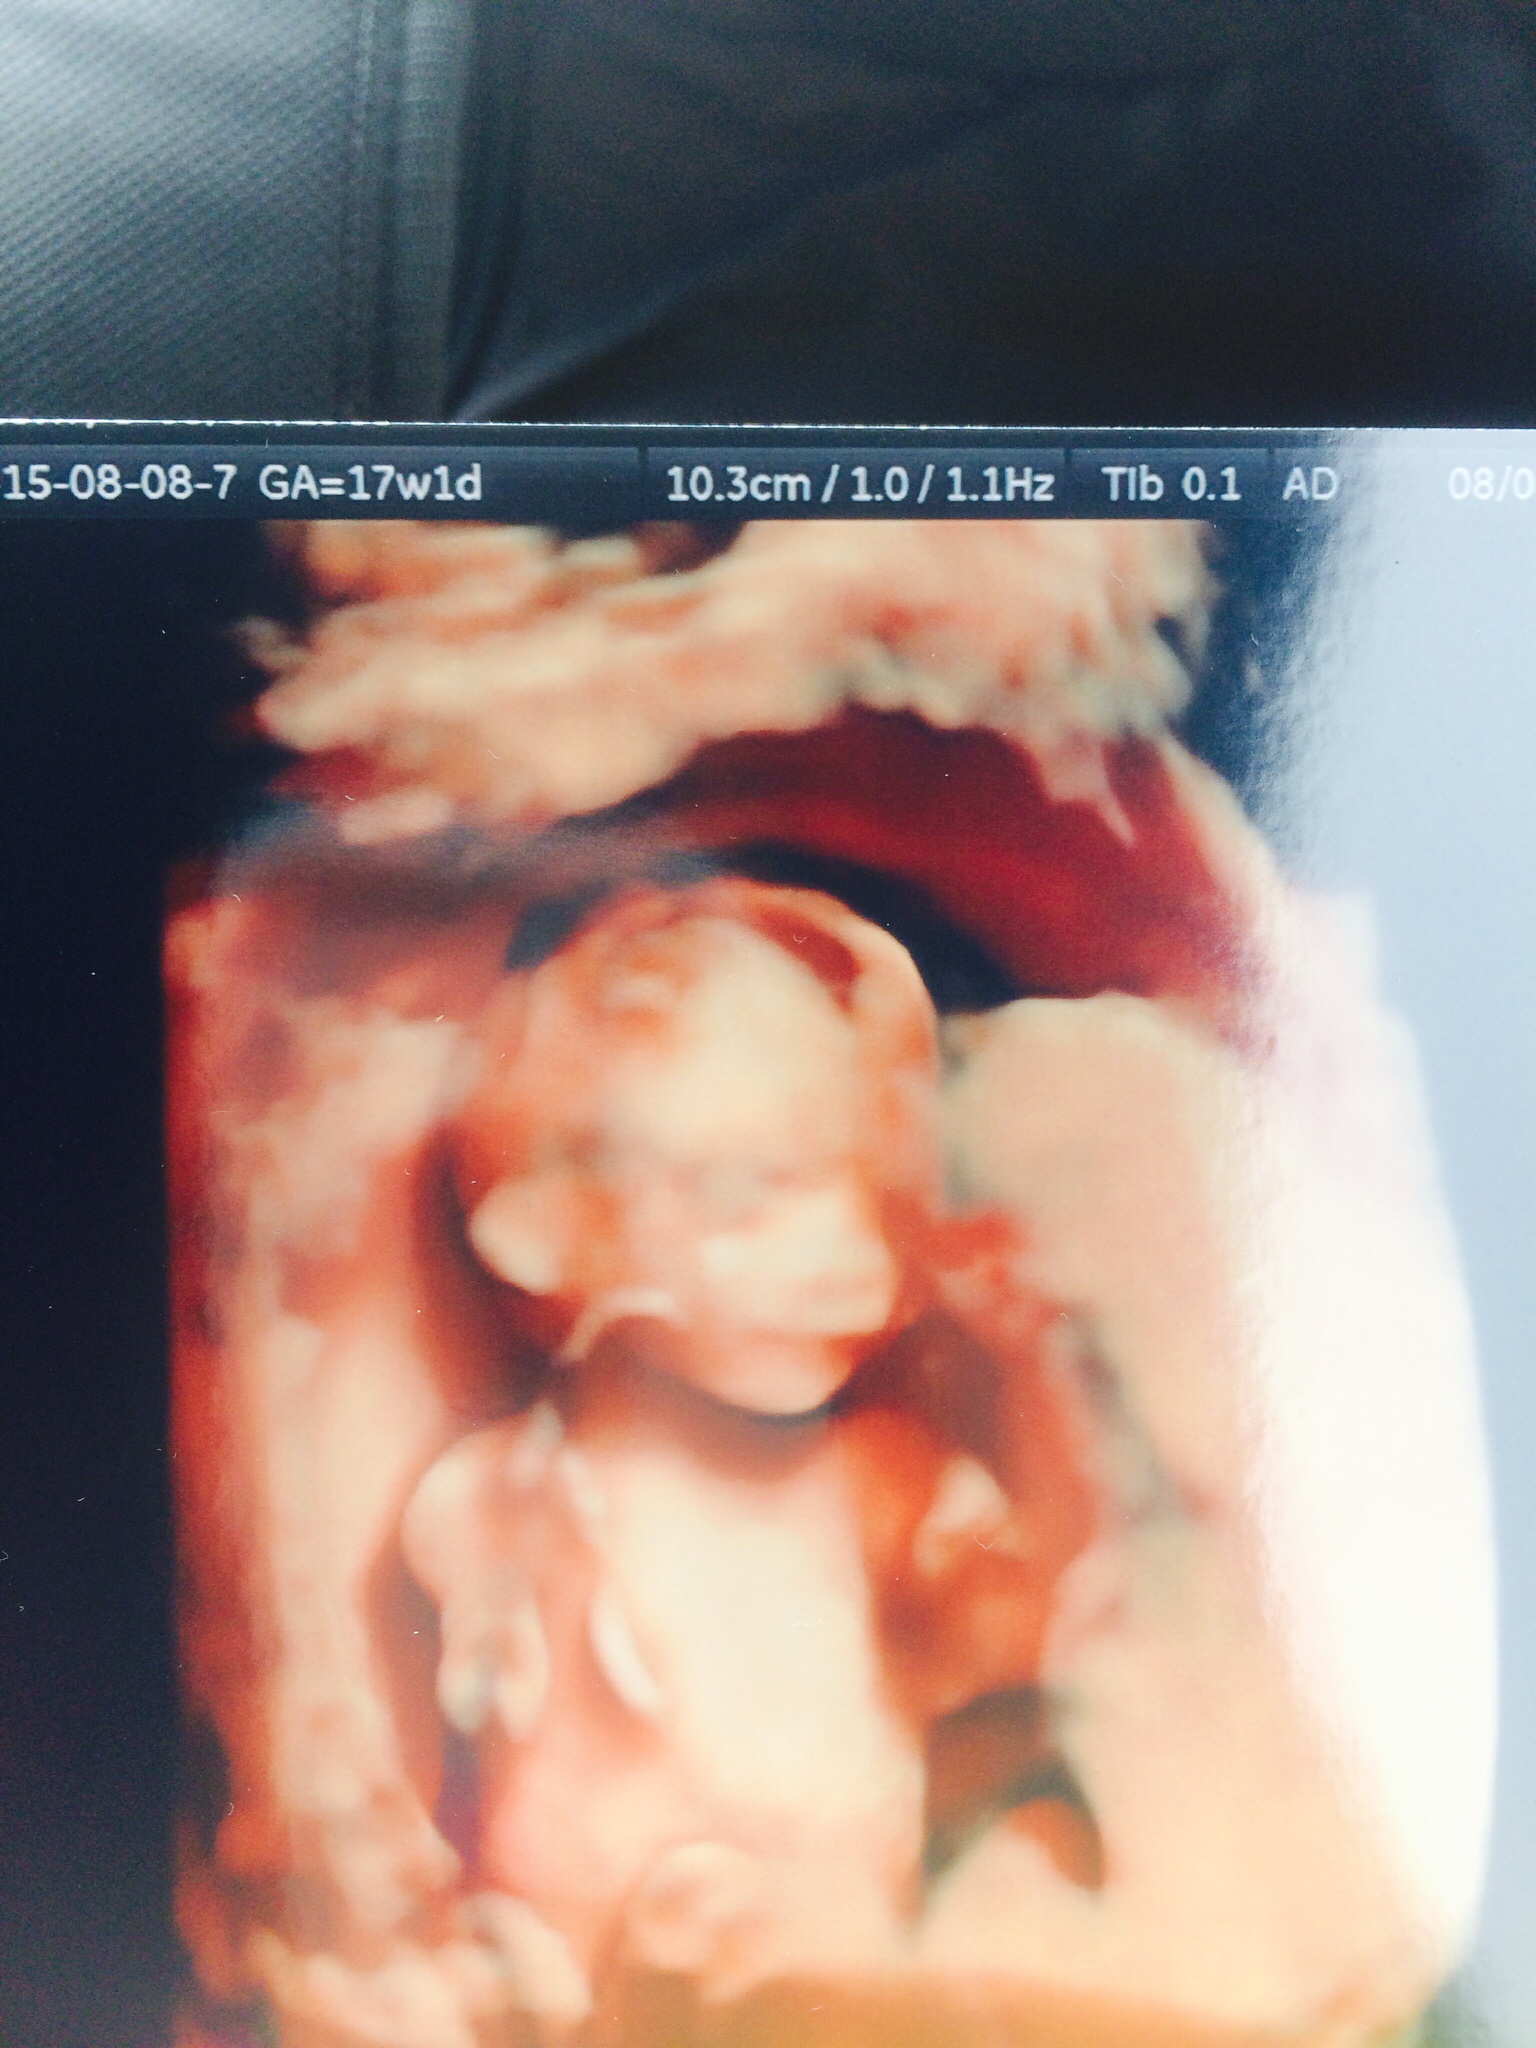

Hi everyone ! I am 17 and 4 days . Did a 3D ultrasound over the weekend . Thought you might want to see what a baby at 17 weeks looks like It's a boy !

It's a boy !